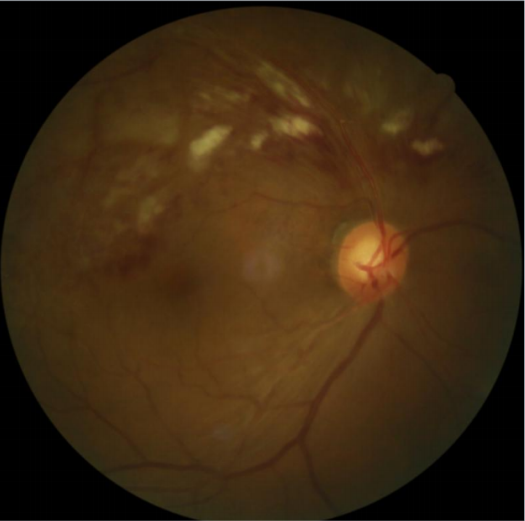

患者劉某,58歲,因右眼視力下降伴變形1月入院。既往有高血壓病,血糖偏高病史,左眼視物不見10餘年(nián),經過眼科主治(zhì)醫(yī)師方(fāng)霏的詳細檢查及眼底造影檢查(chá),發現是患(huàn)上(shàng)了右眼(yǎn)視網膜分支(zhī)靜脈阻塞,右眼黃斑水腫,左眼萎縮(suō)性黃斑(bān)病變。劉大叔入院時右眼視力僅0.1 ,需要使用一種新型的生物製劑(抗 VEGF)治療,方霏主治醫師向患者及家屬交待病情、手術必(bì)要性及相關風險 ,在排除了手術禁忌症後,患者及家屬表示同意手術治療。次日(rì),方霏主(zhǔ)治醫師在(zài)患者表麵麻醉下(xià)進行右眼玻璃體藥物(wù)注射術,術後患者無明顯(xiǎn)特殊不適。4周後複查,右眼黃斑水腫明顯減輕,視力由0.1提高至0.6。玻璃體腔注藥術明顯改善了(le)患者視力,患者劉(liú)大叔表(biǎo)示十(shí)分滿意(yì)。

術後4周眼底照相